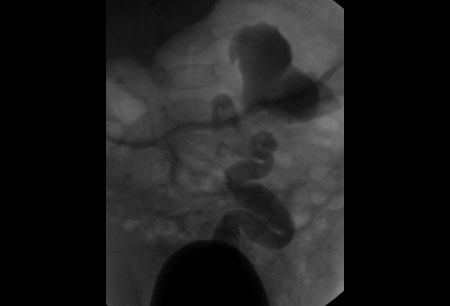

• შარდის გამოყოფის ცისტოურეთროგრამა (VCUG)